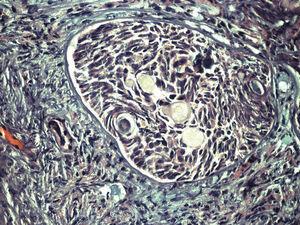

Paciente de 13 años de edad, sin antecedentes personales o familiares de interés. Estadio de Tunner P2-3 y T4, sin menarquia, talla de 1,77 cm y peso 63 kg, que consulta por aumento del perímetro abdominal con dolor. Se describe, tras el estudio de imagen, una tumoración sólida de 13 cm, con evidentes calcificaciones, dependiente de anejo derecho; ascitis a tensión. No presenta adenopatías (fig. 1). En estudios analíticos presenta BHCG de 94,9 mU/ml y perfil hormonal prepúber. Se practicó una laparotomía urgente y se halló una tumoración ovárica derecha de 10 cm, con una cápsula íntegra. El útero y el anejo izquierdos eran normales para edad de la paciente. El diagnóstico intraoperatorio fue tumor de los cordones sexuales-estroma sospechoso de células Sertoli-Leyding. Se le practicó una anexectomía derecha, una omentectomía, una apendicectomía y una biopsia de ovario contralateral más lavados peritoneales. El resultado definitivo de anatomía patológica fue de disgerminoma (fig. 2) para el ovario derecho, gonadoblastoma (fig. 3) para la biopsia del izquierdo, y el líquido peritoneal fue negativo a células malignas. La paciente recibió tratamiento adyuvante con 4 ciclos de bleomicina, etopósido y cisplatino. En la revisión posquimioterapia en nuestra consulta la paciente presentaba: fenotipo femenino normal, genitales externos normales, himen íntegro, vagina de 9 cm de longitud. Los estudios de imagen y los marcadores tumorales analíticos fueron normales, incluido el BHCG. El perfil gonadal prepúber. El estudio del cariotipo desveló un 46XY con gen SRY sin alteraciones, lo cual motivó nuestra propuesta para la gonadectomía izquierda, que se realizó por laparoscopia, y se encontró un resultado anatomopatológico de cintilla gonadal normal. La paciente comenzó un tratamiento con estroprogestágenos cíclicos. Actualmente, se encuentra eumenorreica, libre de enfermedad y con fenotipo femenino P4-T4.

Figura 3. Gonadoblastoma.